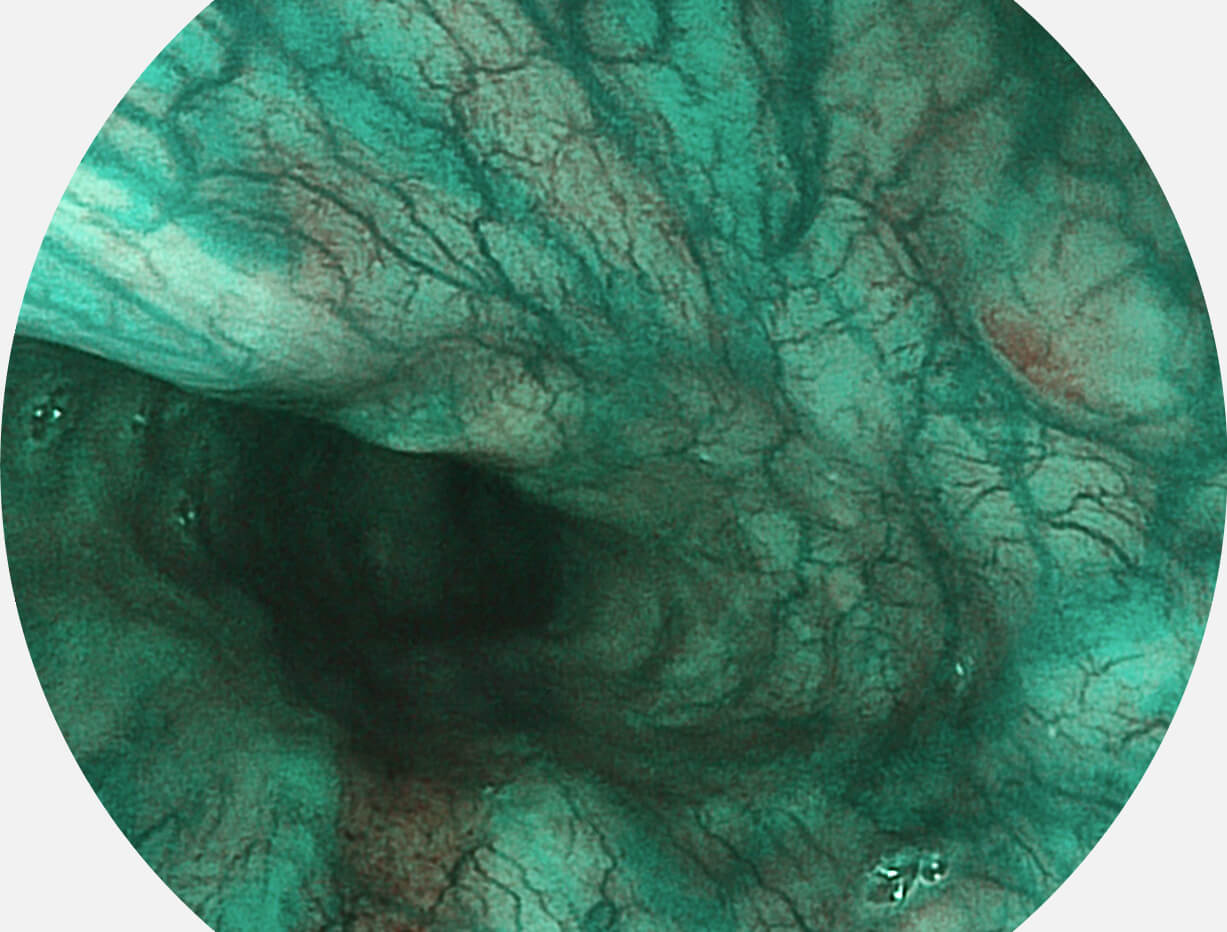

白光图像

SFI图像